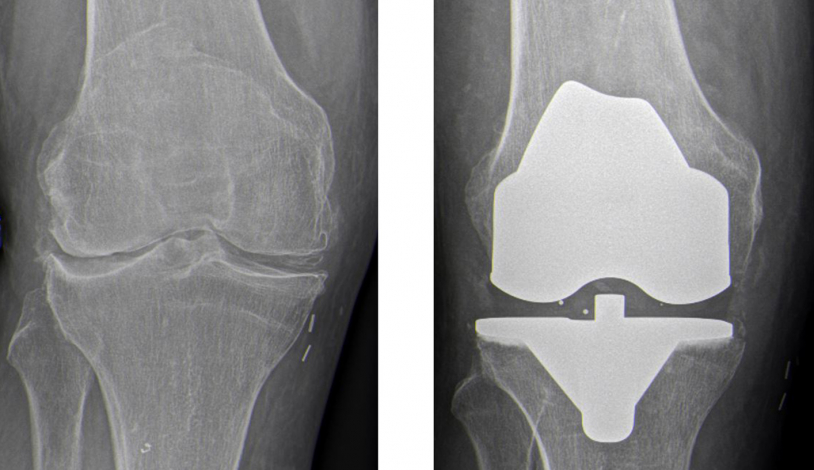

Bikondylärerer Oberflächenersatz am Kniegelenk

Sind beide Gelenksanteile von der Arthrose betroffen und sind alle konservativen Maßnahmen ausgeschöpft, wird eine vollständige Oberflächenersatz-Endoprothese ausgewählt. In aller Regel kommen hierbei Oberflächenersatzprothesen zur Anwendung, die durch die seitlichen Bandstrukturen stabilisiert werden und daher die körpereigenen Bandstrukturen erhalten. Nur bei schweren Schädigungen von Bandstrukturen muss eine Prothese mit zusätzlichen Kopplungselement verwendet werden, die eine langstreckige knöcherne Verankerung benötigt.

Die richtige Knieendoprothese- individuell für jeden Patienten

Die richtige Knieendoprothese wird individuell für jeden Patientin ausgesucht, wobei hier viele Faktoren berücksichtigt werden (Alter, Geschlecht, Knochenqualität und Funktionsniveau). Im Rahmen der Planung wird die Beinachse vermessen und die Prothese digital geplant. Im Rahmen des operativen Eingriffs verwenden wir auch navigationsgestützte (computerassistierte) Systeme. Wir verwenden eine weichteilbasierte Implantationstechnik, die die individuelle Bandspannung berücksichtigt und so zu einem natürlichen Kniegefühl führt. In unsere Klinik kommen hierbei ausschließlich bewährte Implantatmodelle mit durch klinischen Studien sehr gut belegten Langzeithaltzeiten zum Einsatz.